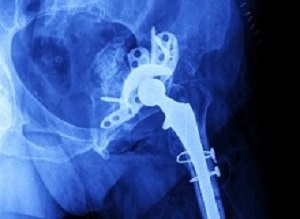

Hip and knee replacements are two of the most common and effective forms of surgery. Yet even in the best-case scenarios, they will ultimately fail due to processes such as infection, fracture, normal wear and tear or reaction to wear particles. In many of these cases, patients require revision surgery which is more prone to failure, associated with poorer function and more expensive than primary surgery.

A hip replacement principally consists of two components, one that replaces the ball and another that replaces the socket. There is variation in how these parts are fixed to the bone, as well as in the materials used to create the bearing (contact) surface. There are two main types of knee replacement used in the UK. A total knee (TKR) replaces all the patient's own joint surface whereas a unicondylar knee replacement (UKR) only replaces the damaged part of the knee. There is considerable variation in how long different designs of hip and knee replacements last and these factors were accounted for in Bristol's study.